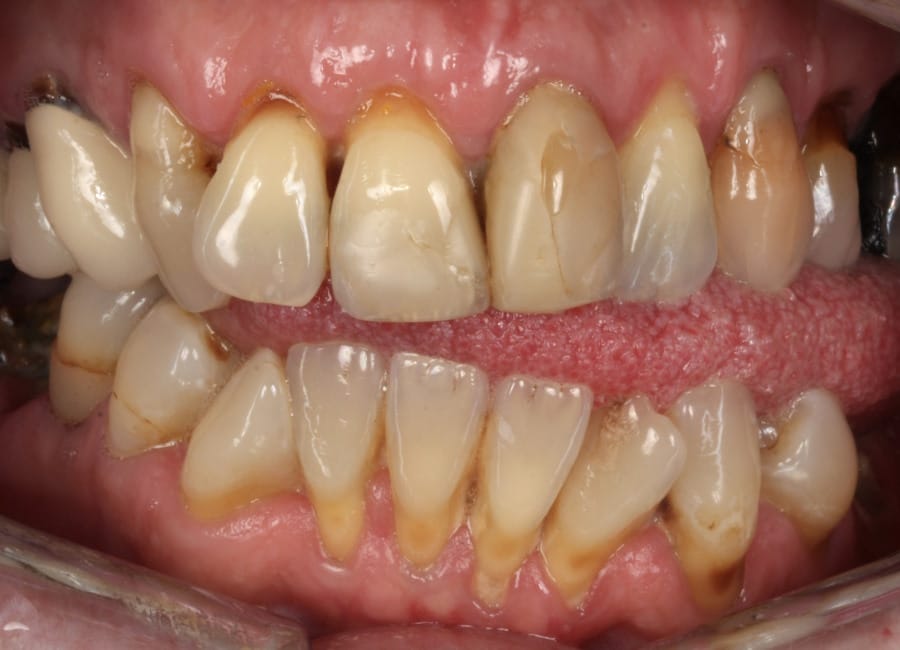

Natalie arrived at Wimpole Street Dental Clinic facing an extremely challenging dental situation. She had several missing and damaged teeth, infections in the bone, and significant bite issues caused by a long-term tongue habit. On top of that, she was a smoker and had developed a strong dental phobia over the years, making it difficult for her to seek help sooner.

Natalie’s treatment began with a comprehensive clinical assessment, including a review of her medical and dental history, a full examination, and analysis of her functional difficulties such as her tongue habit and altered bite. A 3D cone-beam CT scan was then taken to assess bone quality and volume, identify areas of infection, and map important anatomical structures to ensure safe implant placement.

Alongside this, a digital intraoral scan and detailed photographic records were captured. These provided accurate models of her teeth and bite, as well as valuable information about facial proportions and smile aesthetics. Together, these records ensured that planning would address both the functional and cosmetic aspects of her rehabilitation.